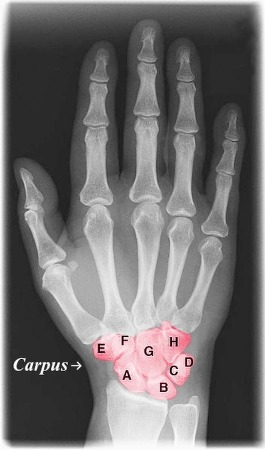

<p>Carpals</p>

Carpals

Form wrist joint with radius and ulna

<p>Form wrist joint with radius and ulna</p>

Scaphoid

Largest bone, attachment to forearm

<p>Largest bone, attachment to forearm</p>

Lunate

Wrist movement and stability, attachment to forearm

<p>Wrist movement and stability, attachment to forearm</p>

Triquetrum

Wrist movement and stability

<p>Wrist movement and stability</p>

Pisiform

Acts as a pulley for tendon leverage

<p>Acts as a pulley for tendon leverage</p>

Trapezium

Thumb range of motion

<p>Thumb range of motion </p>

Trapezoid

Capitate

Hamate

Wrist movement and stability,

<p>Wrist movement and stability,</p>